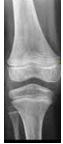

Observe a imagem e responda qual o nome da estrutura indicada.